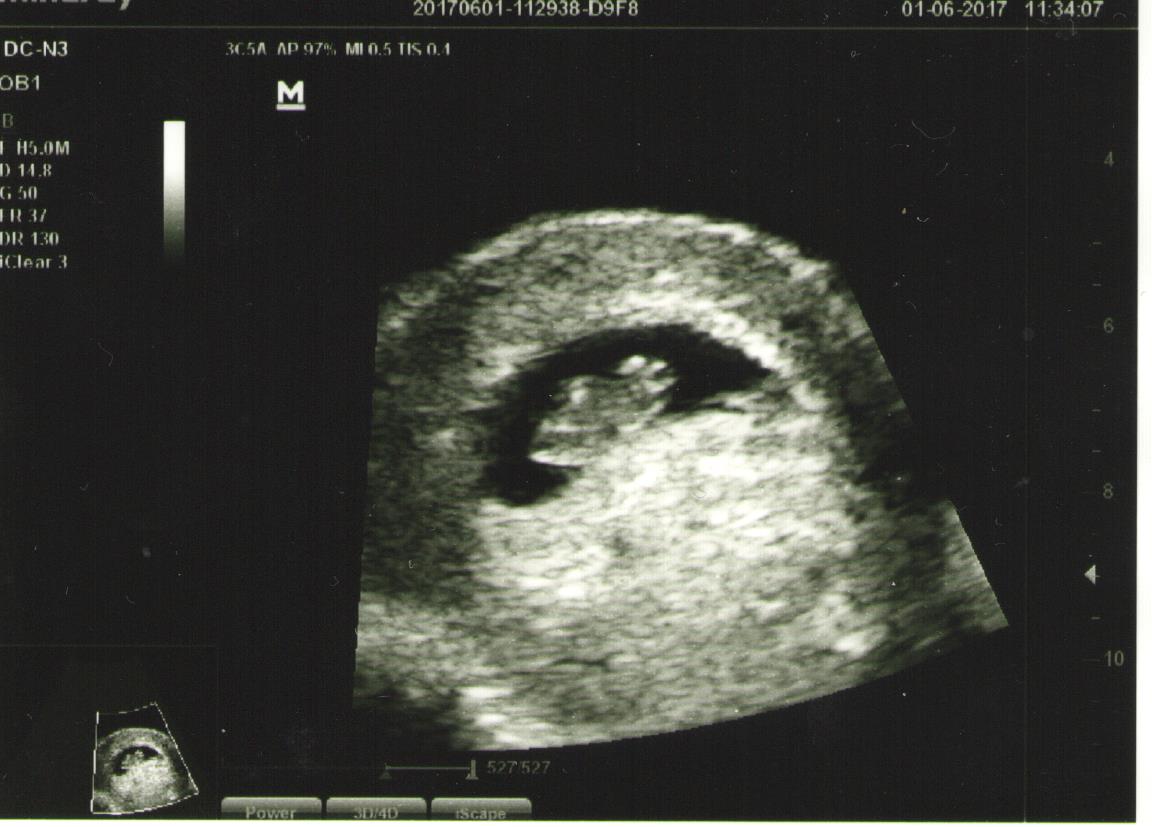

Ik had dus nog een hele voorraad zwangerschapstesten en ovulatietesten over. Nou ben ik natuurlijk helemaal ingelezen in het plannen van het maken van een baby en het doen van testen, dat ik ook wist dat je een ovulatietest kan gebruiken als zwangerschapstest, echter is dit niet een hele betrouwbare methode en blijft een ovulatietest een ovulatietest. Hij spoort een hormoon op dat lijkt op het hCG-hormoon, maar is niet helemaal hetzelfde. Maar ja, ik was zwanger, dus wat moest ik nog met die overige 15 ovulatietesten in de kast? Eh, nou, ik heb ze dus lekker daarna gebruikt om steeds effe te checken of ik nog steeds zwanger was. En gelukkig werden alle testen bij mij steeds donkerder. Maar of dit aan te raden is als je zo onzeker bent of die paar kostbare celletjes van jouw kind in wording goed innestelt, zich vermenigvuldigt en blijven zitten? Dat verschilt per persoon, voor mijn gemoedsrust werkte het wel. Ik ben twee keer enkele druppeltjes bloed verloren, toen waren die testen best fijn, maar die onzekerheid bleef desalniettemin toch hoor. Pas de grootste geruststelling was de eerste echo met een kloppend hartje!

Eerste foto van Guus!